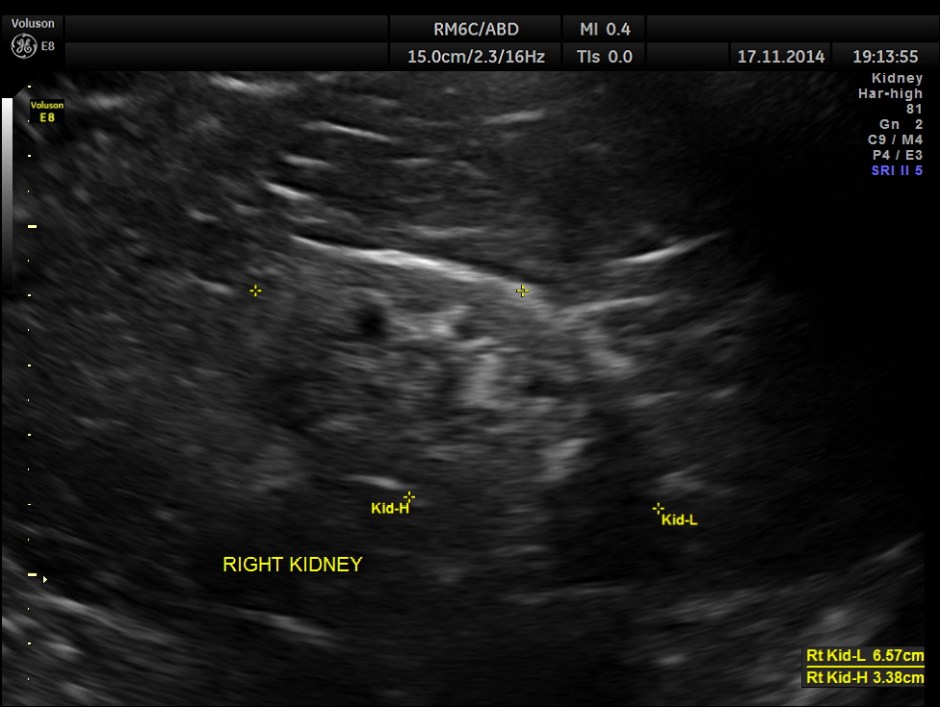

The following pictures show the native kidneys – shrunk with loss of renal architecture , with poor flow seen in Power Doppler.